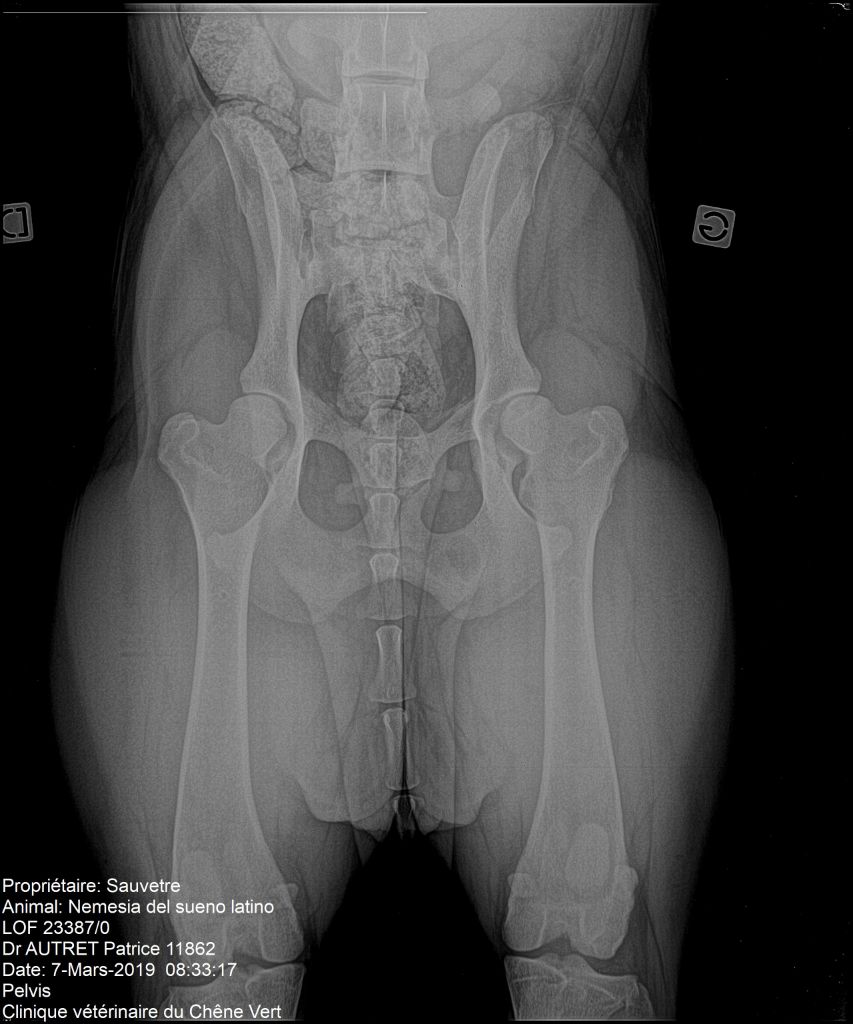

Nemesia del Sueno Latino

Dogo Argentino

Radiographie des hanches

Compte rendu officiel - dysplasie hanches

Dysplasie coudes : : 0/0 officiel Dysplasie hanches : : A/A officiel PEA : : +/+ officiel |